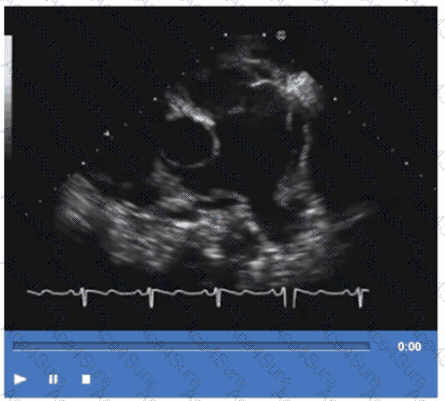

Which vessel is indicated by the arrow on this video?

The video shows a transthoracic echocardiographic apical four-chamber or modified view focusing on the left atrium and adjacent structures. The arrow points to a vessel entering the left atrium from the right side of the image, which corresponds anatomically to the right upper pulmonary vein. The right upper pulmonary vein returns oxygenated blood from the right lung to the left atrium and is visualized in echocardiography as entering the superior-lateral aspect of the left atrium.

The left upper pulmonary vein enters the left atrium on the opposite side. The right and left pulmonary arteries are located anteriorly and superiorly in the mediastinum and are visualized mainly in the parasternal or suprasternal views, not the apical four-chamber.